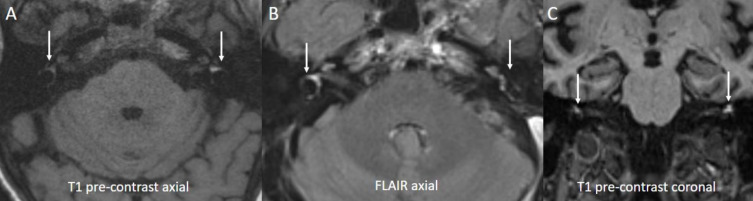

Hyperviscosity syndrome (HVS) is an emergent complication of Waldenström macroglobulinemia (WM) characterized by visual, neurologic, and rarely auditory impairment. We report a 69-year-old female with MYD88 and CXCR4-mutant WM who developed HVS resulting in bilateral blindness and deafness associated with neurologic manifestations including confusion, severe generalized weakness, and imbalance. Ophthalmologic evaluation revealed bilateral central retinal vein occlusion (CRVO), diffuse retinal hemorrhages, macular edema, and serous macular detachments (SMD). Magnetic resonance imaging of the brain showed bleeding in the inner ears. Management was challenging as her WM was resistant to systemic therapies including bendamustine + rituximab (BR) and rituximab + bortezomib + dexamethasone (RVD). Bruton's tyrosine kinase inhibitors could not be used initially due to ongoing lower gastrointestinal bleeding. She required five total sessions of plasma exchange and was finally initiated on zanubrutinib, achieving a partial response. She also received intravitreal bevacizumab with rapid resolution of the retinal hemorrhages but with little improvement of the SMD. She had partial restoration of her hearing in the right ear and only slight improvement in her bilateral visual deficits. The management of HVS in frail, elderly patients with therapy-resistant WM can be challenging. In these cases, plasma exchange is required until an effective systemic therapy can be safely instituted. Genomic profiling is important in the management of WM as it can predict treatment resistance and guide therapeutic decisions.